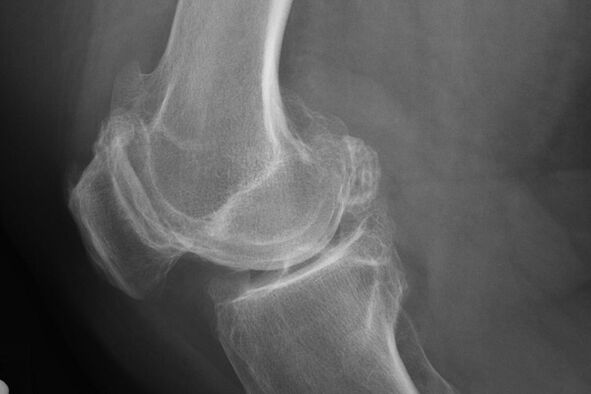

In der Regel tritt die Diagnose der Krankheit in diesem Stadium während einer X -Linie zufällig durch. Darin kann der Arzt einige Unregelmäßigkeiten im Knorpel bemerken. Es ist auch möglich, das Licht zwischen den Teilen der Verbindung zu reduzieren.

X -Ray hilft dabei, Abweichungen im Knorpel zu identifizieren.

Nach der Untersuchung verschreibt der Arzt die Radiographie des Patienten. Dies ist die Hauptmethode zur Diagnose der Arthrose des Kniegelenks eines beliebigen Ausmaßes.

X -Ray gibt dem Arzt eine Vorstellung von den Änderungen, die im Knorpel des Gelenks auftreten. In einigen Fällen kann die Anfangsphase jedoch im Bild nicht definiert werden.

Bei Bedarf kann der Arzt einen wiederholten Durchgang aus einer Radiographie oder einer magnetischen und berechneten Resonanztomographie verschreiben.